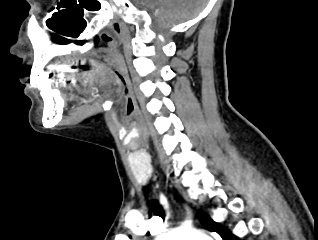

Компьютерная томография является современным высокотехнологичным методом диагностики заболеваний щитовидной железы, основанном на использовании рентгеновского излучения. Процедура отличается быстротой, безболезненностью и проводится без нарушения целостности кожи и расположенных под ней тканей.

КТ щитовидной железы часто используется в диагностике доброкачественных и злокачественных опухолей железы, оценки распространенности процесса, поэтому для улучшения визуализации патологических очагов дополнительно применяется внутривенное болюсное контрастирование. Методика контрастирования позволяет увидеть на снимке опухоли минимальных размеров за счет того, что контраст избирательно накапливается в измененных тканях и обеспечивает яркое изображение патологического очага на фоне здоровых окружающих тканей.  Контрастирование дает возможность определить врачу границы опухоли, ее размеры, степень васкуляризации, точное расположение, особенно это важно при нетипичной (загрудинной) локализации органа.

В наших центрах обследование щитовидной железы выполняется на современных мультиспиральных томографах TOSHIBA AQUILION, оснащенных увеличенным количеством сверхчувствительных детекторов, позволяющих производить множество срезов с минимальной толщиной от 0,5 мм. Инновационные возможности аппаратов обеспечивают получение множества послойных снимков высокого качества и построение на их основе трехмерной модели органа. Кроме того, аппаратура позволяет за счет сокращения времени сканирования минимизировать лучевую нагрузку на пациента.

Мультиспиральная компьютерная томография позволяет точно определить размеры и расположение щитовидной железы, выявить опухолевые образования, оценить их структуру, степень кровоснабжения, взаимодействие с окружающими тканями.